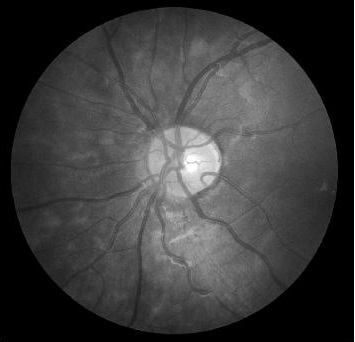

where balances the relative contribution of each feature. was experimentally set by varying it between in steps of and comparing the quality of the resulting SR images on a subset of images. The resulting saliency map in Figure 1 (e) clearly highlights the local retinal structures and thus justifies its use in the GAN cost function.

| (a) | (b) | (c) | (d) | (e) |

4.2 Retinal Blood Vessel Segmentation Results

We present retinal vessel segmentation results on the DRIVE [16], STARE [6] and CHASEDB1 [5] datasets with , and images respectively. Original images and manual annotations () are downsampled by to get and sets of from methods trained on [2]. and the sets of were used to train different state-of-the art U-Nets for vasculature segmentation [1]. The average accuracy () and sensitivity () for is summarized in Table 2. Better ISR methods should give higher vessel segmentation accuracy and performance of gives a lower bound on the segmentation error. ’s performance is closest to , and establishes its superiority over all competing methods. Figures 4 (a)-(h) show results of vessel segmentation on an example image. ’s performance is most similar to as is evident from the areas of inaccurate segmentation highlighted by yellow arrows. Most of the methods do not segment the finer vasculature structures, while SSR and SR-RF are unable to segment some of the major arteries.

| (a) | (b) | (c) | (d) | (e) | (f) | (g) | (h) |